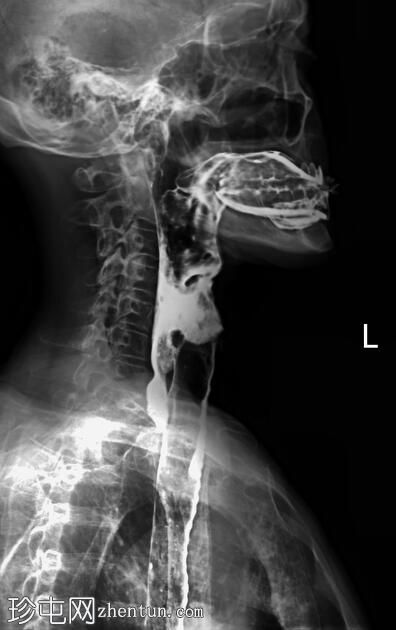

正位和侧位图像显示造影剂在咽部积聚,并伴有钡剂误吸至气道和支气管树。未见

肺

实变。

此外,胸椎存在退行性改变,表现为终板硬化和边缘骨赘形成。

透视图像显示钡剂误吸覆盖喉部和气管支气管树。